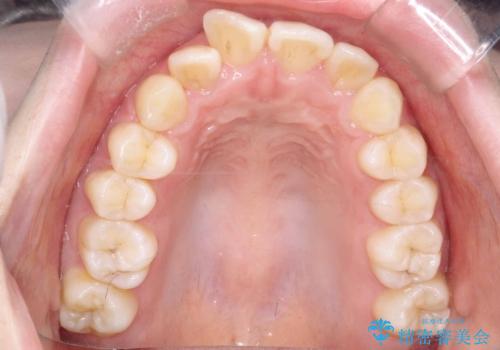

- 「歯のでこぼこと捻じれを治したい」を主訴に来院された患者様です。矯正検査の結果、上顎前歯がかなり唇側傾斜という結果になったので上下左右4番を抜歯をしワイヤー矯正で治療を行いました。

抜歯矯正でしたが順調に治療が進み2年で矯正治療を終えることが出来ました。歯のでこぼこや捻じれが治り、口元も下がって患者さんも大変満足されていました。